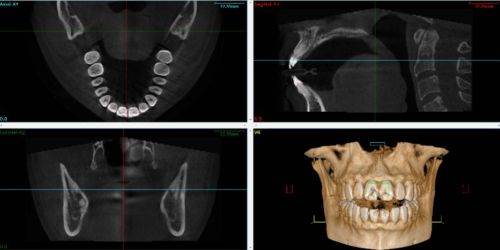

The Cone Beam uses a conical X-ray beam of constant width. The principle is identical to that of conventional radiology, which practitioners use every day. The device rotates around the object under examination, projecting onto a digital sensor with each pulse. The cone beam allows the volume of the object to be obtained directly by computer calculation from the multiple 2D projections acquired during the rotation of the device. Output data is in DICOM2 format.

For TMJ3 analysis, wide-field scans including the entire maxilla are recommended. Moreover, file quality is directly linked to the segmentation procedure and attention must be paid to data integrity at the TMJ bone structures level